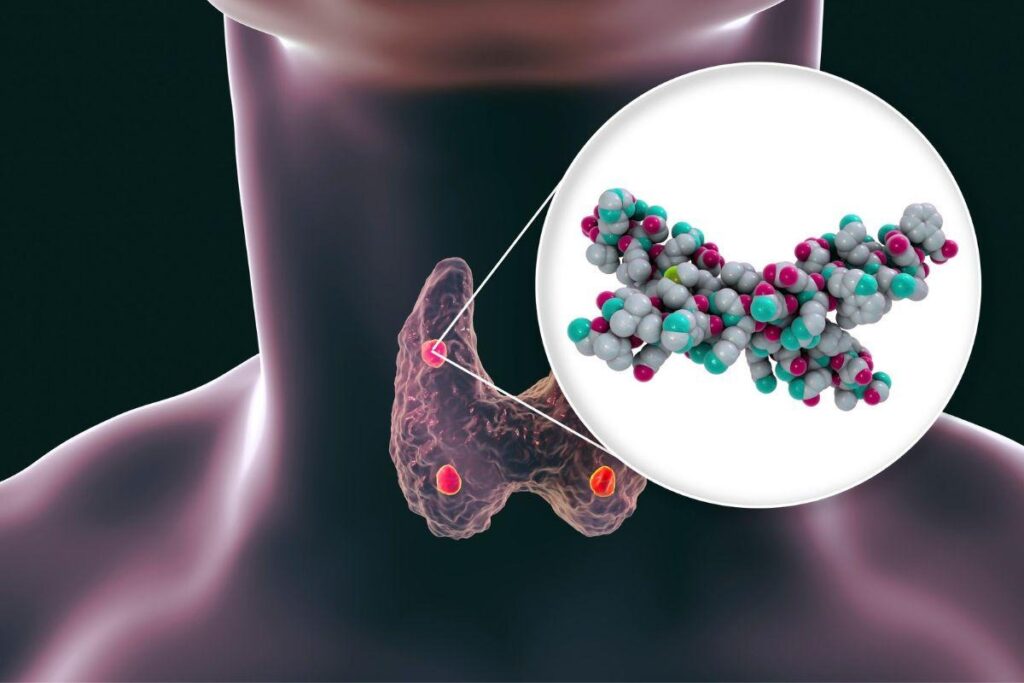

Ambas envolvem o funcionamento das glândulas paratireoides, presentes em número de quatro e próximas à tireoide, que são responsáveis pela produção do paratormônio (PTH), hormônio essencial para o equilíbrio do cálcio, do fósforo e da saúde óssea.

As paratireoides são pequenas glândulas localizadas atrás da tireoide e têm como principal função regular os níveis de cálcio no sangue por meio da produção do PTH.

A liberação do PTH ocorre, principalmente, em resposta à queda do cálcio no sangue. Quando os níveis de cálcio diminuem, sensores presentes nas paratireoides detectam essa alteração e estimulam imediatamente a liberação do hormônio. Em contrapartida, quando o cálcio está adequado ou elevado, a produção de PTH é reduzida, mantendo o equilíbrio metabólico.

O PTH atua em três órgãos principais. Nos ossos, estimula a liberação de cálcio para a circulação. Nos rins, reduz a perda de cálcio pela urina e aumenta a eliminação de fósforo. Já no intestino, o PTH atua de forma indireta. Ele promove a ativação da vitamina D no rim, e esta por sua vez, aumenta no intestino a absorção do cálcio, proveniente da alimentação.